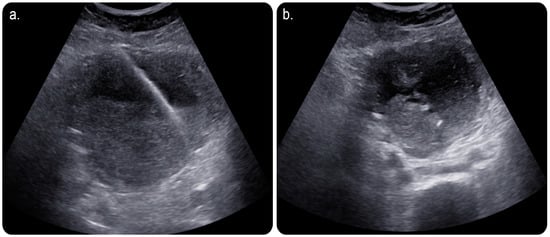

Day 1 post-procedure, the patient underwent an ultrasound scan, which revealed significant improvement in the endometrial fluid collection. The patient was taken to an Angio Suite, wherein a wire was advanced through the pre-existing drainage catheter that was inserted in a retrograde fashion. Thus, the fluid collection was diverted through the vagina outside the body. The percutaneous drain was removed and replaced after advancing the wire through the cervix until it exited outside the vagina, with another transvaginal catheter inserted over the wire using a similar concept of body flossing technique (Figure 4).

Day 2 postoperatively, an ultrasound scan showed further improvement with no residual fluid. The postoperative leukocyte count was normalised, and all laboratory results were normal. Subsequently, the drain was removed, and the patient was discharged.

Figure 4. (a) Fluoroscopic image of the pelvis showing a wire being introduced through the same access to be directed into the cervix with a trial to negotiate the obstruction. (b) Fluoroscopic image showing a catheter being used to direct the wire into the cervix. (c) Fluoroscopic image after successfully crossing the cervical stenosis/occlusion with free passage of contrast through the vagina. The wire can be seen projecting through the vagina to outside the body. A stretching balloon was used to dilate the stenosed/obstructed area of the cervix to prevent possible future recurrence of the stenosis. (d) Grey-scale ultrasound image performed on day 1 postoperatively, showing significant improvement in the collection with minimal residual amount of the collection.